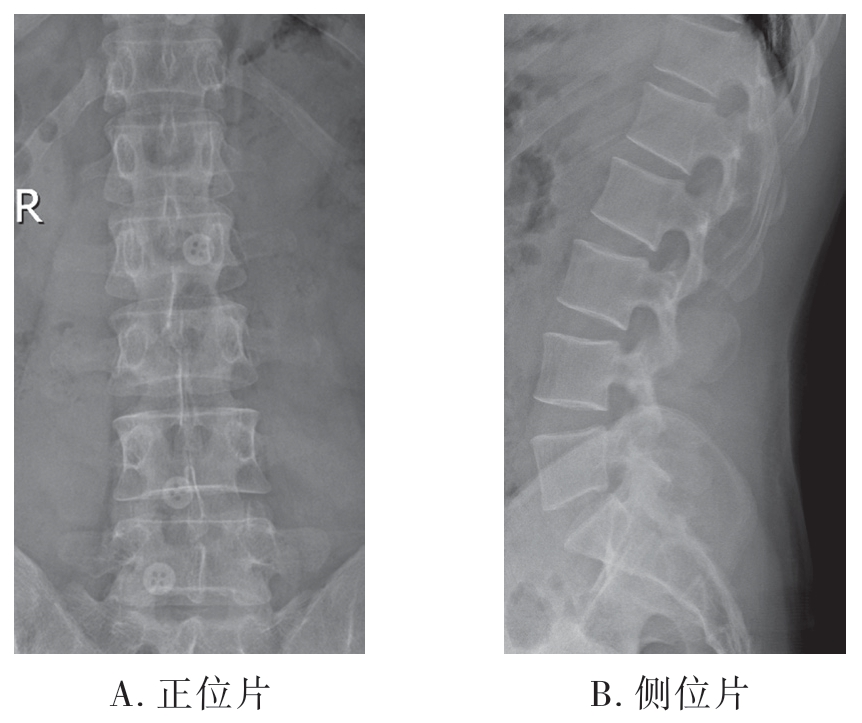

(3)腰椎X线片

1)正位X线片:可显示腰椎的椎体、椎间隙、小关节、棘突、横突、骶髂关节、骶椎及周围软组织(图7-2-4A)。

2)侧位X线片:可显示腰椎椎体、椎间隙、小关节、棘突、椎间孔及周围软组织(图7-2-4B)。

图7-2-4 腰椎X线片